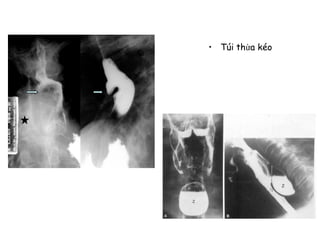

Túi thừa thực

quản:

-Đẩy

-Kéo

• Túi thừa kéo

• Túi thừa đẩy